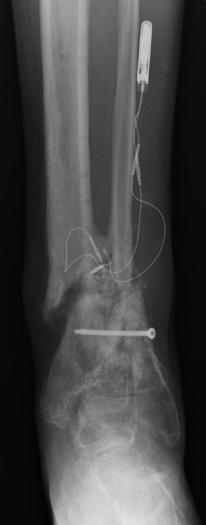

X-Rays Following Hyperextension of Left Ankle (January 31st 2006)

These x-rays were taken following a fluke event where Liam hyperextended his left ankle while playing an XBox 360 video game. As can be

seen in the images there are two (2) breaks that were produced from the hyperextension. One of the tibia bones has a hairline break and

the bone piece that spontaneously fused the tibia to the fibula has snapped. It took almost 2 weeks to determine that these breaks had

occurred. Due to Liam’s unique pain threshold and the lack of visible indicators, a break was not considered. Just another senseless

accident that resulted from the use of a violent video game. ;-) Yeah, right...